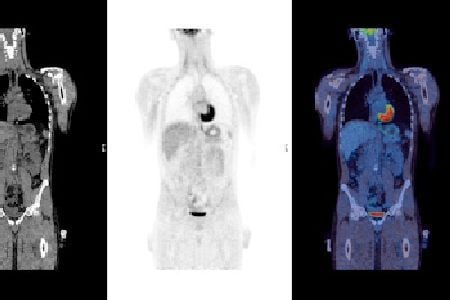

Most of us hear the word metastasis and picture cancer cells taking a road trip to distant lands. In reality, its a grim journey: cancer cells break away from the primary tumor, travel through the lymphatic system or bloodstream, and set up camp in other organs. The first usual stop is the lymph nodes, then the liver, lungs, and sometimes the brain or bones.

Studies from the National Center for Biotechnology Information (NCBI) show that , followed closely by the liver. When the liver is involved, it cant filter toxins effectively, leading to jaundice, bleeding, and eventually liver failure.

Common Metastatic Pathways

Esophageal cancer typically spreads through two highways:

- Lymphatic route: Cancer cells crawl into nearby lymph nodes, then spill into the larger lymphatic network.

- Hematogenous route: Cells enter the bloodstream, hitching a ride to distant organs.

OrganSpecific Impact

Each organ reacts differently:

- Liver: Loss of detoxification, leading to jaundice and bleeding disorders.

- Lungs: Shortness of breath, coughing up blood, or rapid pneumonia.

- Brain: Headaches, vision changes, or seizuressigns that the cancer has crossed the bloodbrain barrier.